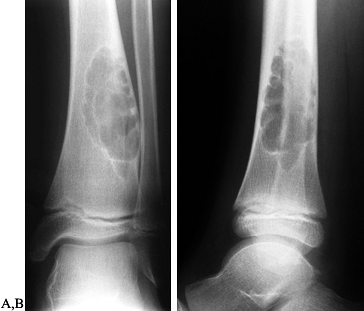

juxtacortical, expanding zone of radiolucency at the

epiphyseometaphyseal end of a long bone (Fig. 127.3A, Fig. 127.3B).

The tumor is a well-delineated lesion with irregular endosteal margins.

There is usually no reactive host bone at the periphery of the lesion.

According to the staging system for benign bone tumors, the lesion most

typically presents as an active (stage 2) or aggressive (stage 3)

tumor. The tumor frequently extends to the subchondral bone of the

articular surface and destroys the surrounding cortex, extending into

the soft tissue. Because of the rapid expansion, a periosteal reaction

is seldom seen. The combination of substantial destruction and poor

margination may suggest malignancy.

![]() |

|

Figure 127.3. AP radiograph (A)

of a giant cell tumor (GCT) of bone shows a radiolucent lesion of the lateral distal femur involving the epiphysis and the metaphysis. It has destroyed the cortex although the periosteum is intact, and it is well delineated although not well marginated. In the lateral film (B), it is apparent that the lesion extends down to the subchondral bone distally and along the patellofemoral joint. This has the typical appearance of a GCT of bone. AP (C) and lateral (D) radiographs show the postoperative findings in this patient who was treated with extensive curettage, burring of the cavity, and packing with PMMA bone cement and reinforcing metal rods. |

Following adjuvant treatment, reconstruct the defect using bone graft, bone graft substitute, or PMMA (130). Pack PMMA from the articular surface outward (Fig. 127.3C,D).

As the PMMA sets, use iced saline lavage to help control the

temperature at the subchondral bone–cement interface to prevent thermal

damage

P.3391

to

the articular surface. Use radiopaque cement to facilitate follow-up

examinations for recurrence. If cryotherapy has not been used

autogenous and/or allogenic bone graft may be used as an alternative to

PMMA (16).